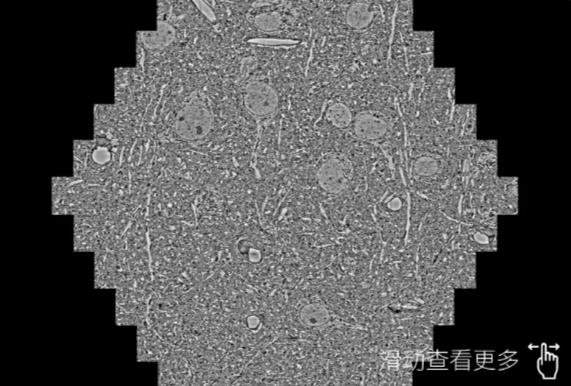

鼠脑切片。左图使用贵州蔡司贵州扫描电镜MultiSEM706对165μmx143pm面积区域成像,耗时仅需1.5秒。右图为鼠脑切片中30μm区域放大效果。样品由芝加哥大学B.Kasthuri提供。

使用蔡司高速贵州扫描电镜MultiSEM对1mm²人脑皮层组织进行高分辨成像,并对其中的各种细胞结构进行三维重构分析。左图展示了2x3mm²组织平面中锥体神经元的三维重构效果。右图显示了局部体积神经元三维重构。图像由哈佛大学chtman实验室提供,渲染图由D. Berger 制作。